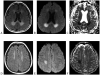

Neurologic complications of cancer are common and are frequently life-threatening events. Certain neurologic emergencies occur more frequently in the cancer population, specifically elevated intracranial pressure, epidural cord compression, status epilepticus, ischemic and hemorrhagic stroke, central nervous system infection, and treatment-associated neurologic dysfunction. These emergencies require early diagnosis and prompt treatment to ensure the best possible outcome and are best managed in the intensive care unit. This article reviews the presentation, pathophysiology, and management of the most common causes of acute neurologic decompensation in the patient with cancer.